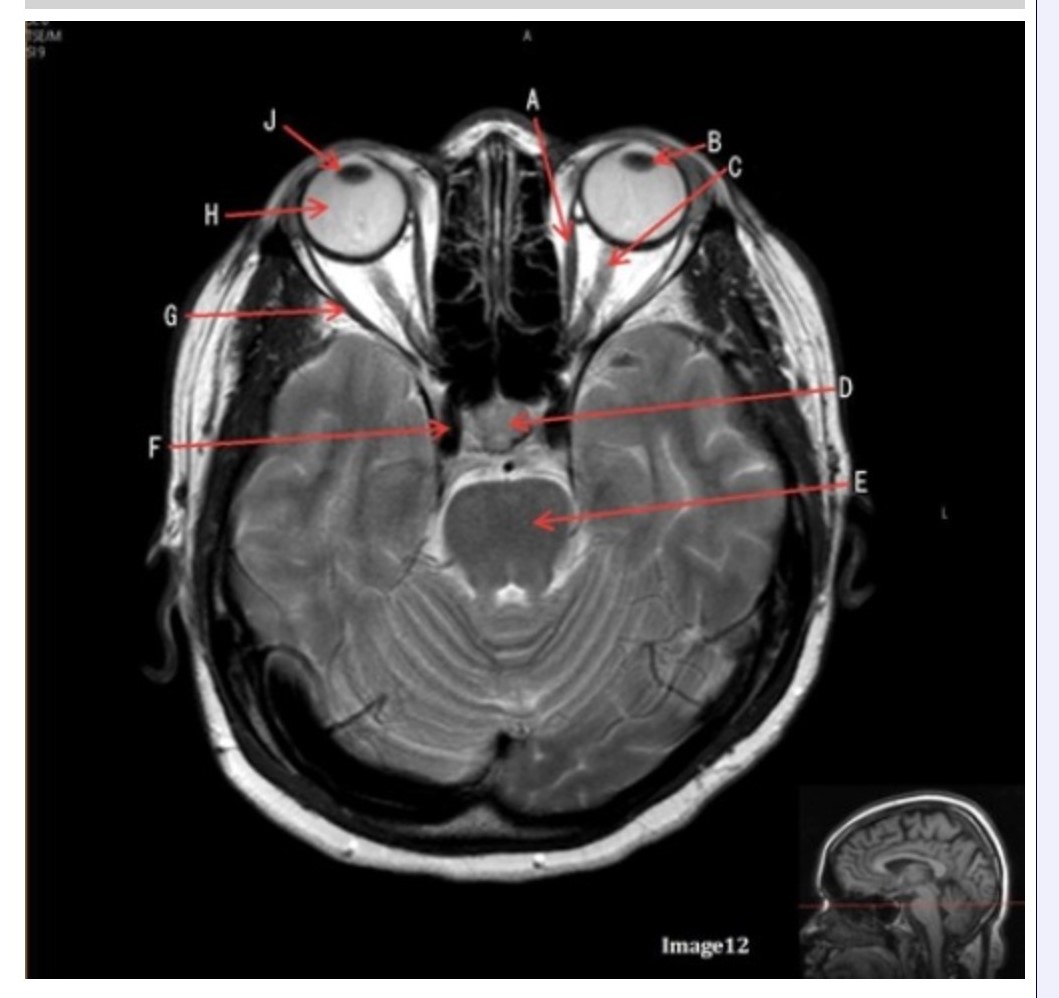

Letter H in Image 12 is pointing to:

A. Lens

B. Lateral rectus muscle

C. Medial rectus muscle

D. Internal carotid artery

E. Globe

Letter B in Image 12 is pointing to:

A. Left optic nerve

B. Lateral rectus muscle

C. Medial rectus muscle

D. Lens

E. Midbrain

Letter J in Image 12 is pointing to:

A. Globe

B. Lateral rectus muscle

C. Medial rectus muscle

D. Right lens

E. Left lens

Letter F in Image 12 is pointing to:

A. Lens

B. Lateral rectus muscle

C. Medial rectus muscle

D. Internal carotid artery

E. Globe

Letter C in Image 12 is pointing to:

A. Left optic nerve

B. Lateral rectus muscle

C. Medial rectus muscle

D. Lens

E. Midbrain

Letter D in Image 12 is pointing to:

A. Optic nerve

B. Pituitary gland

C. Globe

D. Lens

E. Midbrain

Letter G in Image 12 is pointing to:

A. Lens

B. Lateral rectus muscle

C. Medial rectus muscle

D. Internal carotid artery

E. Globe

Letter E in Image 12 is pointing to:

A. Optic nerve

B. Pituitary gland

C. Globe

D. Pons

E. Left lens